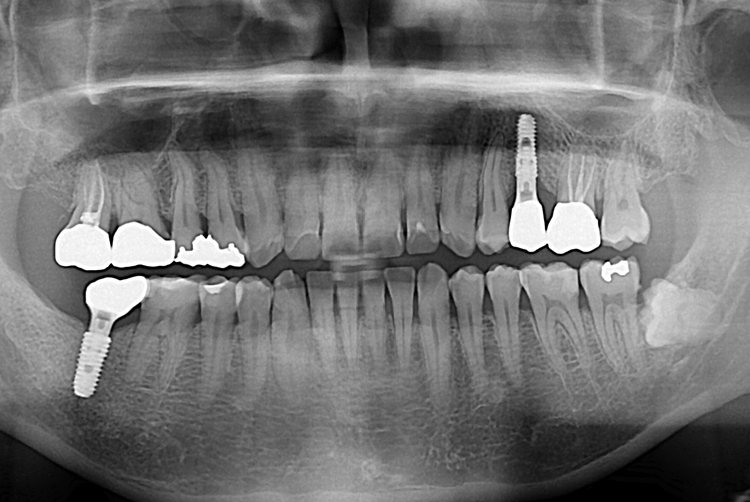

[임플란트] 어금니 임플란트

치료후 : 2016-09-07

세종치과는 많은 환자와 다양한 케이스를 바탕으로

항상 편안한 임플란트 수술을 제공하고자 노력하고,

오래동안 튼튼히 쓸 수 있는 임플란트 수술을 가장 큰 목표로 삼고 있습니다.